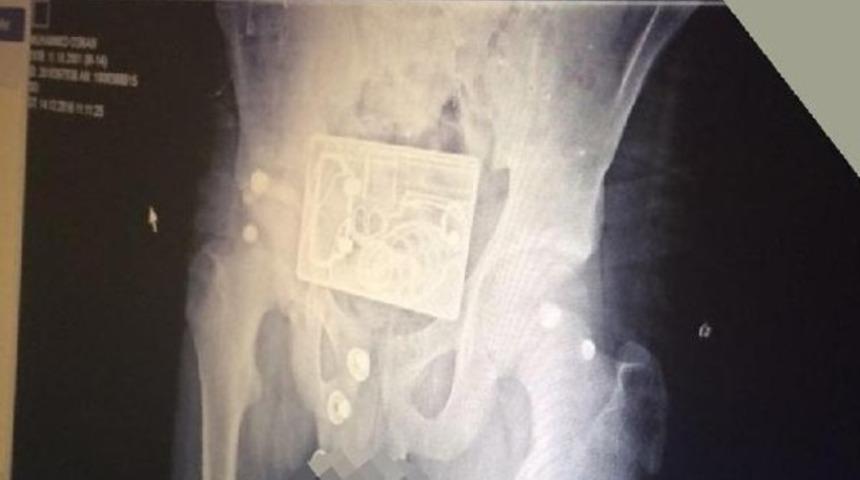

Bacağındaki rahatsızlık nedeniyle hastaneye gelen Azerbaycan uyruklu M.O. röntgen servisine gönderildi. Burada pantolonu çıkarmadan çekilen röntgen filmine gencin taktığı metal tokanın görüntüsü de yansıdı.

Tokadaki tabanca, el bombası ve mermi desenlerini gencin beline bağladığı bomba zanneden görevli durumu polise bildirdi.